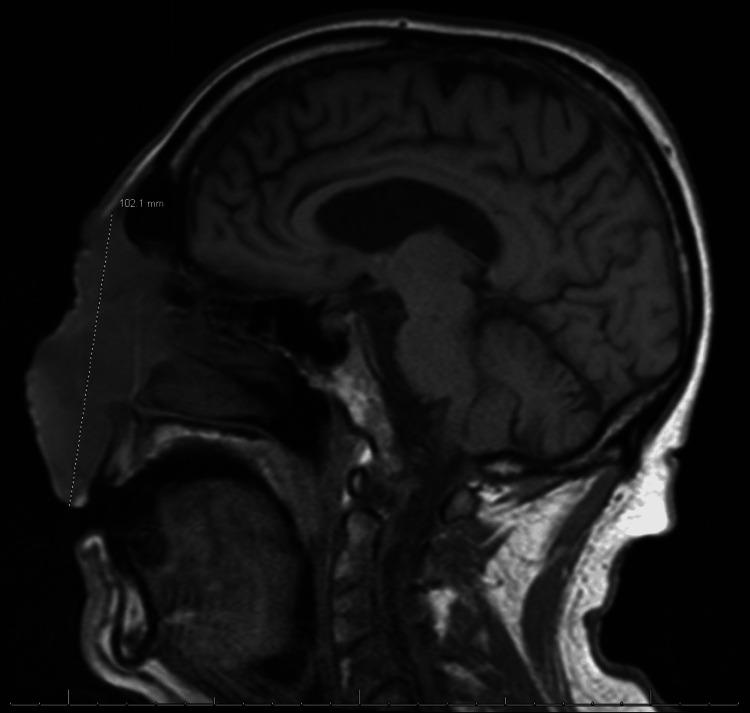

Nodular melanoma is an aggressive subtype of malignant melanoma, accounting for a disproportionate number of melanoma-related deaths due to its rapid progression and early metastatic potential. Despite its distinct histopathological characteristics, clinical diagnosis can be challenging, particularly when the presentation mimics other conditions. We present the case of a 67-year-old male whose facial nodular melanoma was initially treated as an invasive fungal infection due to overlapping clinical and radiographic features, including osseous destruction, soft tissue invasion, and systemic involvement. The patient underwent antifungal therapy, which resulted in acute kidney injury from amphotericin B, prior to a definitive diagnosis by histopathological analysis. This case highlights the importance of maintaining a broad differential diagnosis for atypical facial lesions, especially those with aggressive features or poor response to initial therapies. Early biopsy and tissue evaluation are essential to distinguish malignant melanoma from infectious or inflammatory conditions and to ensure timely, appropriate management.

结节性黑色素瘤是恶性黑色素瘤的一种侵袭性亚型,因其进展迅速和早期转移潜能,在黑色素瘤相关死亡中占比过高。尽管其具有独特的组织病理学特征,但临床诊断可能具有挑战性,尤其是当临床表现与其他疾病相似时。我们报告一例67岁男性病例,其面部结节性黑色素瘤最初因临床和影像学特征重叠,包括骨质破坏、软组织侵犯和全身受累,而被当作侵袭性真菌感染进行治疗。在通过组织病理学分析明确诊断之前,患者接受了抗真菌治疗,该治疗导致了两性霉素B引起的急性肾损伤。该病例强调了对非典型面部病变保持广泛鉴别诊断的重要性,尤其是那些具有侵袭性特征或对初始治疗反应不佳的病变。早期活检和组织评估对于区分恶性黑色素瘤与感染性或炎症性疾病以及确保及时、恰当的治疗至关重要。